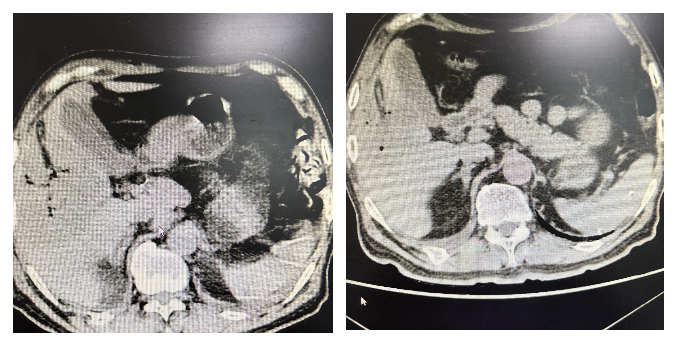

术后患者生命体征稳定,意识清醒。因脓毒血症原因,转入重症医学科继续接受高级生命支持。术后第2天患者感染指标就出现显著下降,随即转入普通病房继续治疗。影像学检查显示,术后第5天肝内胆管积气消失,脓腔明显缩小;术后第20天仅见引流管及少量积气。目前患者已顺利康复出院。

患者术后5天和20天的CT显示图